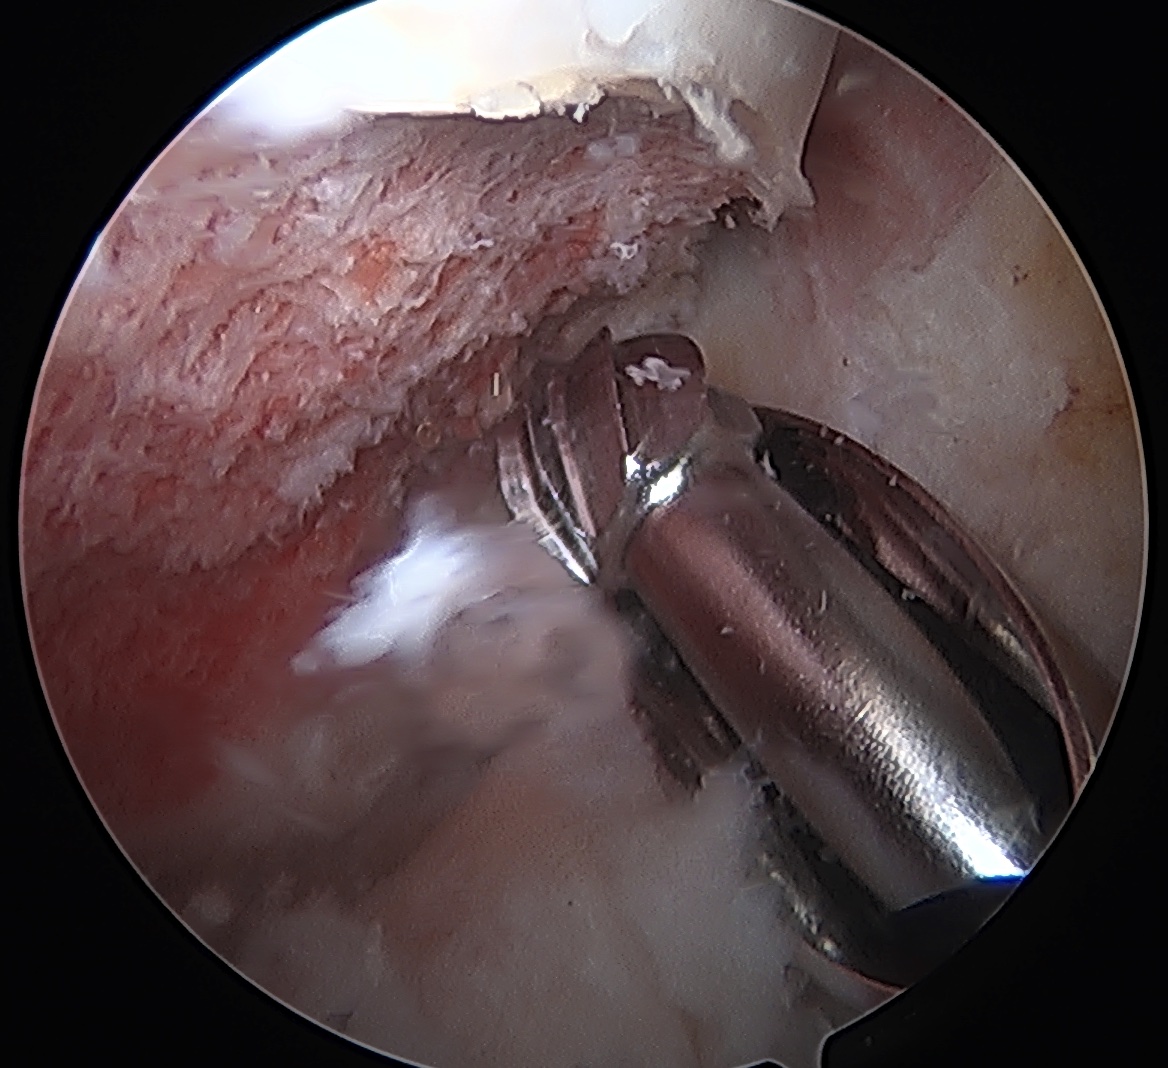

CAM resection

Capsule

- distal capsule suspension sutures / parachute technique

- T capsulotomy - better for large Cam lesions, needs repair

Placing distal capsule sutures to allow parachute technique / distal capsule suspension to expose Cam

T capsulotomy to expose large Cam at head neck junction